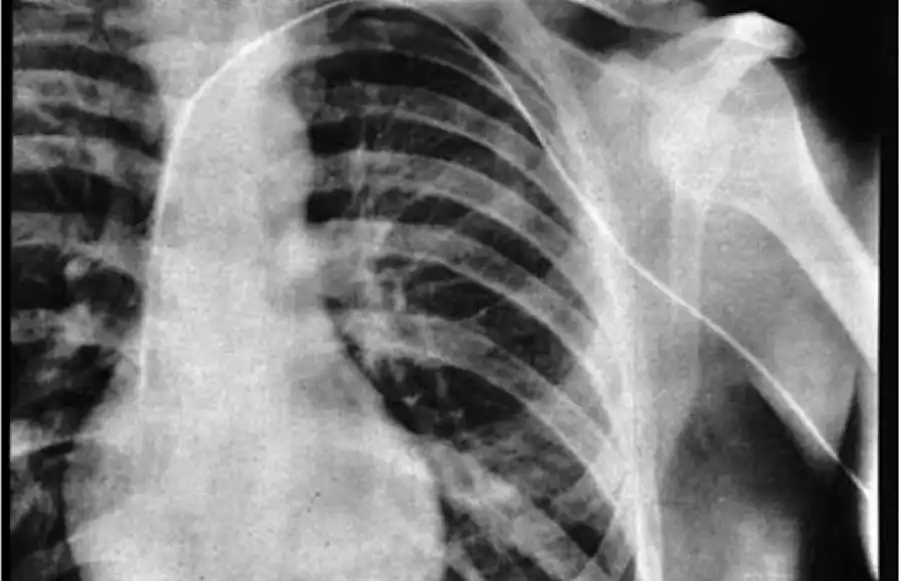

Вернер Фореман. Один из самых известных экспериментов над собой связан с немецким вра¬чом, который выдвинул гипотезу, что катетер можно вставить в сердце, чтобы доставлять лекарства и красители для рентгеноло¬гических исследований.

Никто не мог точно знать, убьет ли это человека, поэтому в 1929 году он вставил полую иглу себе в руку, через которую стал продвигать катетер до тех пор, пока он не достиг предсердия.

Фореман был награжден Нобелевской премией.